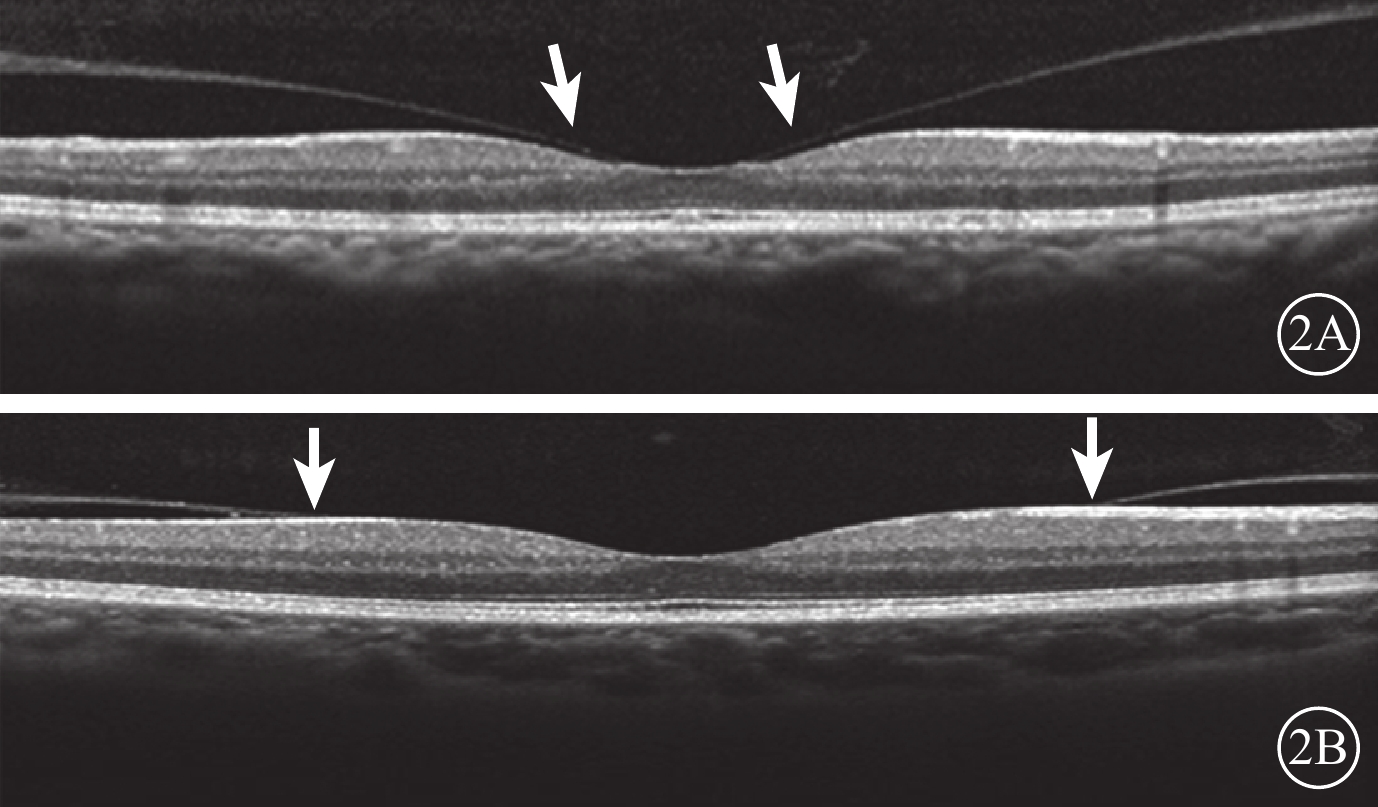

末次隨訪時,34只研究眼中,VMI異常12只眼。其中,廣泛型VMA 5只眼,局灶型VMA 2只眼,C-PVD 3只眼,MEM 2只眼;合并存在C-PVD、MEM 1只眼。與治療前比較,共有6只眼VMI發生變化(圖3)。34只對照眼中,VMI異常13只眼。其中,廣泛型VMA 5只眼,C-PVD 7只眼,MEM 1只眼。與治療前比較,共有6只眼VMI發生變化(圖4)。治療前研究眼中局灶型VMA 3只眼,其末次隨訪時發生C-PVD 2只眼。治療前對照眼中局灶型VMA 2只眼,末次隨訪時均發生C-PVD(表1)。

末次隨訪時,34只研究眼中,VMI異常12只眼。其中,廣泛型VMA 5只眼,局灶型VMA 2只眼,C-PVD 3只眼,MEM 2只眼;合并存在C-PVD、MEM 1只眼。與治療前比較,共有6只眼VMI發生變化(圖3)。34只對照眼中,VMI異常13只眼。其中,廣泛型VMA 5只眼,C-PVD 7只眼,MEM 1只眼。與治療前比較,共有6只眼VMI發生變化(圖4)。治療前研究眼中局灶型VMA 3只眼,其末次隨訪時發生C-PVD 2只眼。治療前對照眼中局灶型VMA 2只眼,末次隨訪時均發生C-PVD(表1)。